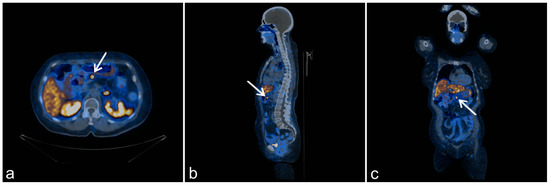

In 2017, a second relapse of the neuroendocrine tumor was observed; (68Ga) Ga-DOTATATE positron emission tomography/computed tomography (PET/CT) revealed the pathological expression of somatostatin receptors in an epigastric lymph node and in the second segment of the liver. In 2018, abdominal CT detected hypodense focal lesions in the liver and enlarged mesenteric lymph nodes (Figure 2a–c). Moreover, mesenteric lymph nodes and a focal lesion in the liver hilum (size 18 × 15 mm) were detected. A non-functional tumor (18 × 10 mm) was detected in the left adrenal gland. Magnetic resonance imaging of the liver revealed lesions in the eighth segment (20 × 30 mm) and the second segment (11 mm). These were suspected to be metastatic lesions.

Figure 2.

Clinical and radiological presentation of the index patient. Transverse (a), axial (b), and sagittal (c) fused (68Ga) Ga-DOTATATE positron emission tomography (PET)/computed tomography (CT) images of a pancreatic insulinoma with metastases (arrows), cutaneous manifestations of MEN1 syndrome (d) with collagenoma, and hyperpigmented skin lesions (arrows).

Fluorine-18 fluorodeoxyglucose PET/CT (FDG-PET) revealed a metabolically active region in the liver and in the mesogastric region, either in the small intestine or in a lymph node. Subsequently, (68Ga) Ga-DOTATATE PET/CT was performed. In the liver, no pathological accumulation of the tracer was found; however, lymph nodes along the lesser curvature of the stomach showed pathological expression of SSTR. At this point, the patient did not consent to any further invasive diagnostic procedures. Physical examination revealed the presence of cutaneous collagenomas and hyperpigmented skin lesions (Figure 2d).